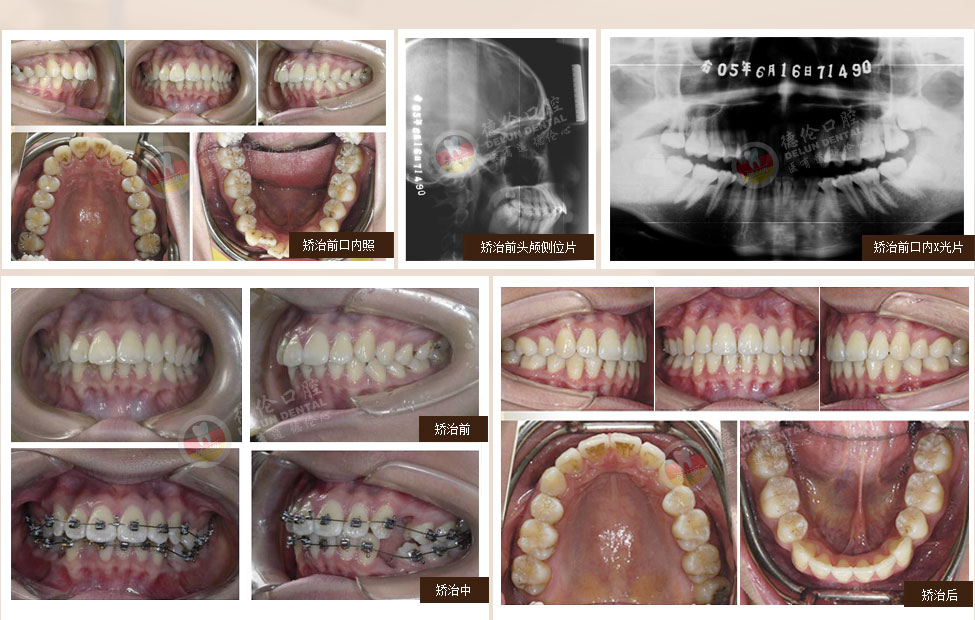

過去第一磨牙很早齲壞或缺失的患者只能拔除齲牙進行缺牙修復,若同時第三磨牙因阻生反復引起牙齒發炎疼痛,那么還要面臨拔除智齒恐懼??娫洪L通過多年臨床研究最終發明一種通過豎立智齒來代替齲壞或缺失的第一磨牙的方法,該技術刊登在2006全球權威口腔正畸學術雜志上,也稱為:“繆”院長的“妙技術”。

針對人群:下頜第一磨牙齲壞或缺失且下頜第三磨牙阻生。

備注:第一磨牙即六齡齒,人長出的第一顆恒牙。第三磨牙即智慧齒,最晚長出的恒牙。